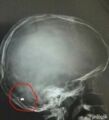

إخراج طلقة من رأس صبي بعفيف